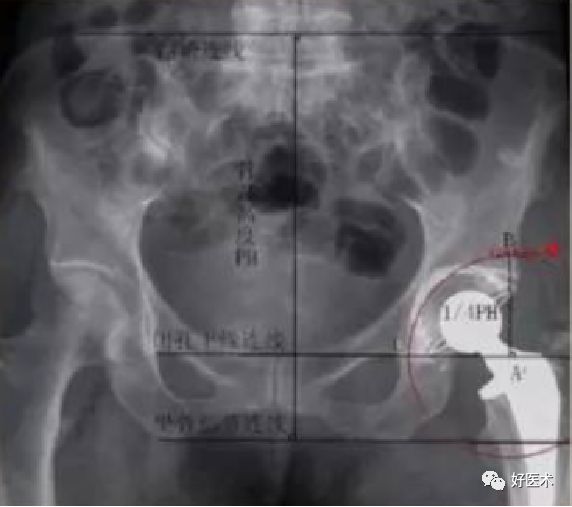

Pradhan法测量

-

在X线片上标记髋臼杯口形成椭圆的最大直径D,在最大直径的1/5处标记点M,经过点M做最大直径的垂线并与椭圆相交于两点A、B。测量最大直径D和点M到点A或B的距离P,则髋臼前倾角为arcsin[P/ (0.4D)]

Hubard法

在X线上两侧闭孔上缘连线与通过髋臼外上角垂线的焦点为A,点A向上1/4骨盆高度处为B,再在闭孔连线上作点C,使AC=AB。以A为中心,以AB为半径作圆弧BC。正常髋臼应在此等腰三角扇形内。